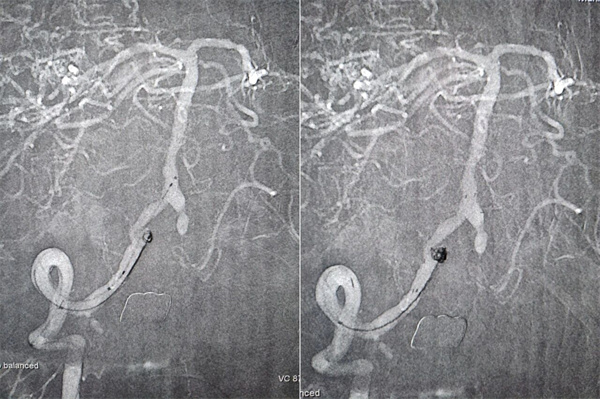

第二步,处理动脉瘤,拆除不定时炸弹。医生将微导管超选择进入动脉瘤腔内,依次填入数枚弹簧圈,直至动脉瘤完全栓塞,不再显影。因为动脉瘤瘤颈宽,故于载瘤动脉内植入了支架以达到致密栓塞,降低复发率。

第四步,最终验证。再次造影显示:狭窄消失,支架位置良好。动脉瘤不显影,弹簧圈致密填塞。